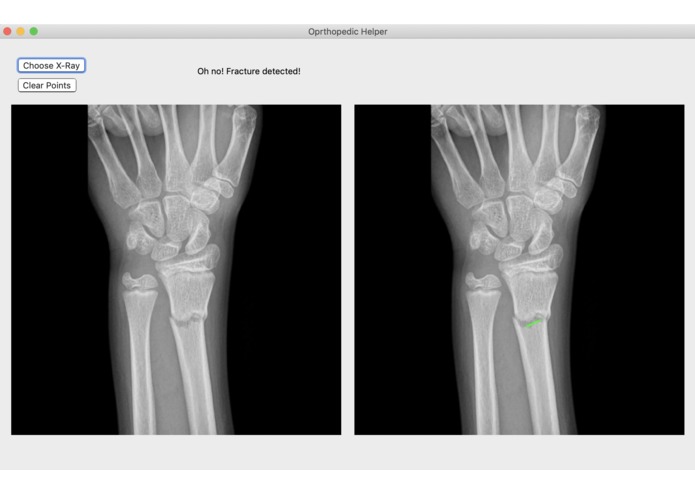

Broke Detector is a simple tool to help analyze the site of wrist injury. It helps doctors decide a) whether the bones are broken or not (which is admittedly very simple for humans, but not for computers) and b) provides tools such as a protractor to provide an objective measurement of how misaligned bones are. Broke Detector aims not to replace the orthopedist, but to aid them.

The actual detection algorithm is the guts of this project (no machine learning involved). The process is as follows: Thresholding: Reasons for this will be listed in the next section, we did this using color histograms to determine the percentile of certain pixel values. Edge detection: We used a simple Söbel kernel (however, not the default opencv one) to handle edge detection, as it was simple to detect only horizontal edges. Hough transform: This is the guts of the algorithm, which decides where horizontal lines are in the X-Ray. It sounds dumb, but choosing the lowest isolated horizontal line almost always results in finding the break in the bone. Flask: We developed a locally hosted web application which supports uploading from the computer. The HTML formatted site displays the results of the Python calculations.

While we were very passionate about doing something involving the X-rays, there were a couple issues with our process. The common state-of-the-art solutions to a problem like this would be stuffing a bunch of data into a faster R-CNN and let it handle the detection. However, we lacked both the volume and consistency of data to make this a reality: many of the research papers that tackled this problem partnered with a medical office, which would provide them a lot of consistent and annotated images to work with. Because of the hodgepodge of different variables that differ with each image we ripped off of Google images, we had to use techniques like color thresholding, as the brightness of what was bone and what was background differed from image to image. Even now, the algorithm isn't quite perfect. It still struggles to detect fractures that are close to the end of the radius/ulna.